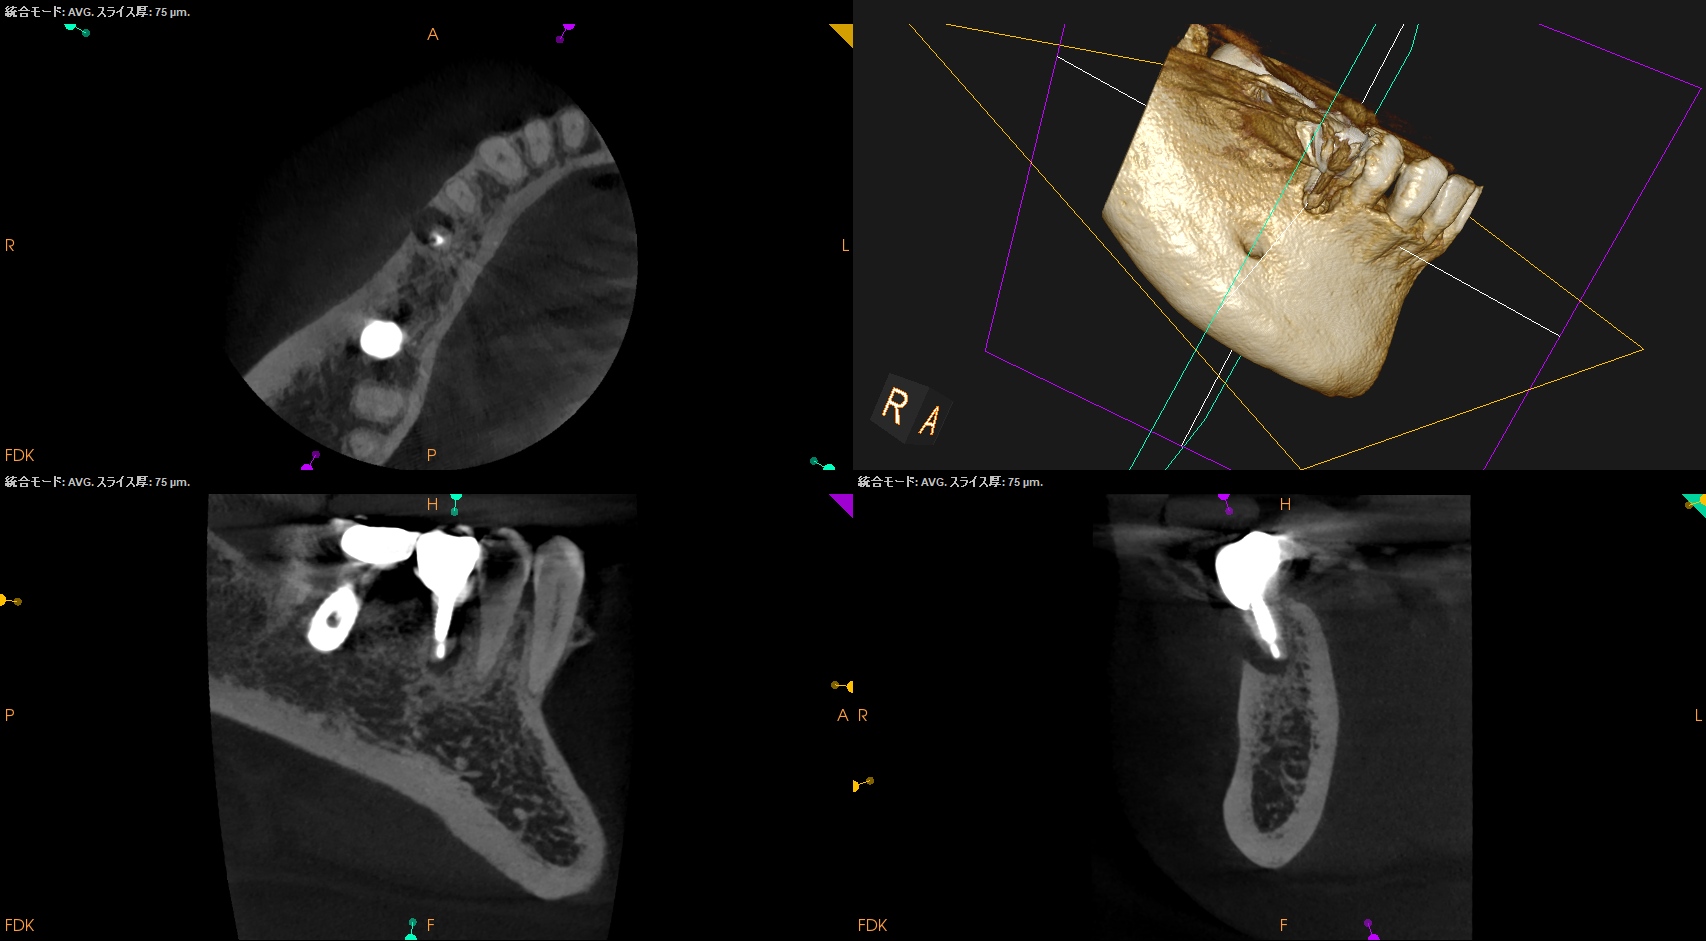

術後にPA, CBCTを撮影した。

問題はないだろう。